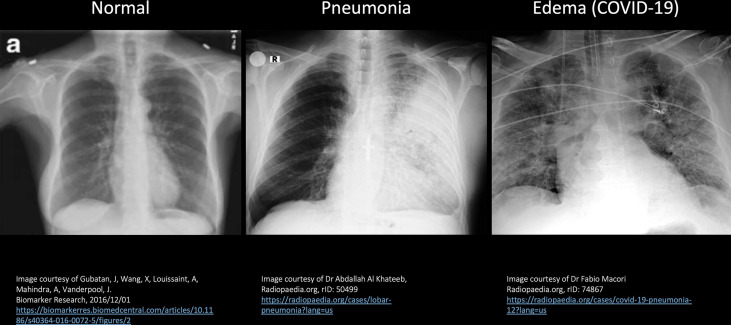

Fig. 4 shows a sequence of Chest X Ray images starting with normal lungs on the left, left lung pneumonia in the middle and COVID-19 pneumonia on the right image, all of which can differentiate disease processes and identify images more likely to be seen with COVID-19 (Gubatan et al., 2016). On the normal patient X-ray (left image), you see that the lungs are filled with air and there are streaks of normal blood vessels which are the white lines going through the lungs. On the middle image, you can see that the right lung is fairly normal, much like what we saw on the left, but the left lung shows this very white area in a highly demarcated area. This so-called consolidation, restricted to one lung, is very typical of a bacterial pneumonia. COVID-19 is a viral pneumonia (right image) which presents with whiteness occurring on both sides. Notice that the lungs are not completely opaque, and you can partially see through the lung, which is termed the ‘Ground-glass’ appearance. Ground-glass opacification/opacity (GGO) is a descriptive term referring to a region of hazy lung radiopacity, often fairly diffuse, in which the edges of the pulmonary vessels may be difficult to appreciate (Hansell et al., 2008). The ground-glass appearance is sort of what you would see with shower glass. This patient is also quite ill as you can see that there is an endotracheal tube placed to support breathing and there is also a visible intravenous line in the superior vena cava (CVP line).

Fig. 4.

Sequence of chest X-Ray images.